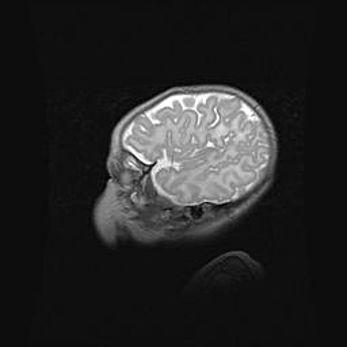

Множественные кисты обоих полушарий головного мозга, наибольшая из них в правой затылочной области. Ассиметричная атрофическая гидроцефалия.

Возраст: 7 месяцев

Вес: 5660 г

Пол: мужской

Окружность головы: 41,5 см

Срок гестации: 28-29 недель

Кисты головного мозга развиваются в результате многоочаговых некрозов вещества мозга и возникают вследствие перенесенной перинатальной инфекции, менингитов, энцефалитов, асфиксии, родовой травмы, расстройств мозгового кровообращения различного генеза. Образованию кист в веществе головного мозга плодов и новорожденных способствуют такие факторы, как высокое содержание в нем воды, недостаточная (или отсутствие) миелинизация и слабая астроглиальная реакция на повреждение.

Кисты могут сочетаться с гидроцефалией и другими поражениями головного мозга.